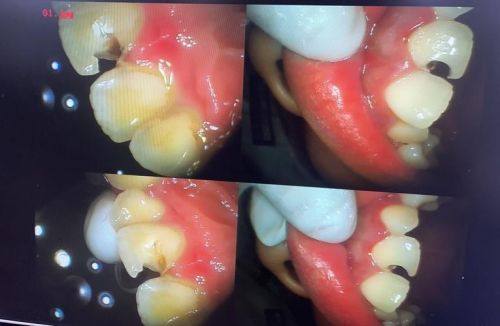

1. 我之前牙齿有个小龋洞,一直没在意,后来越来越重度。来到于钦睿口腔,医生仔细检查后,制定了补牙方案。补牙过程中,医生操作特别熟练,没有任何疼痛感。补完牙后,牙齿修复了正常,感觉特别好,以后看牙就认准这家了。